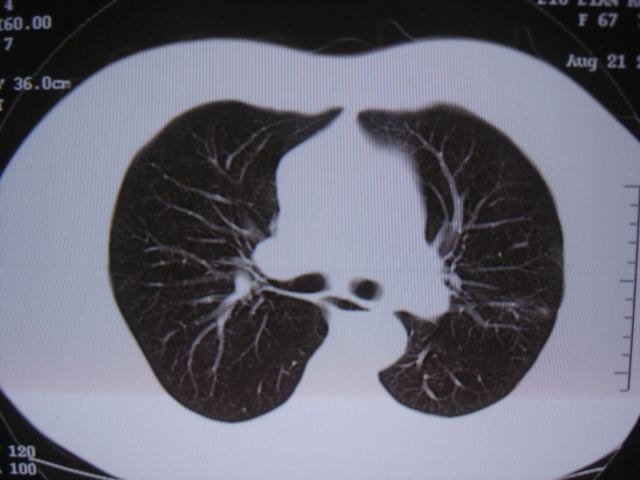

第三次ct2009.8.21

病灶与胸膜成直边征,考虑炎症假瘤可能性大。

考虑左肺上叶炎症感染(炎性假瘤可能)。

考虑左肺上叶炎症感染,以炎性假瘤可能性大。